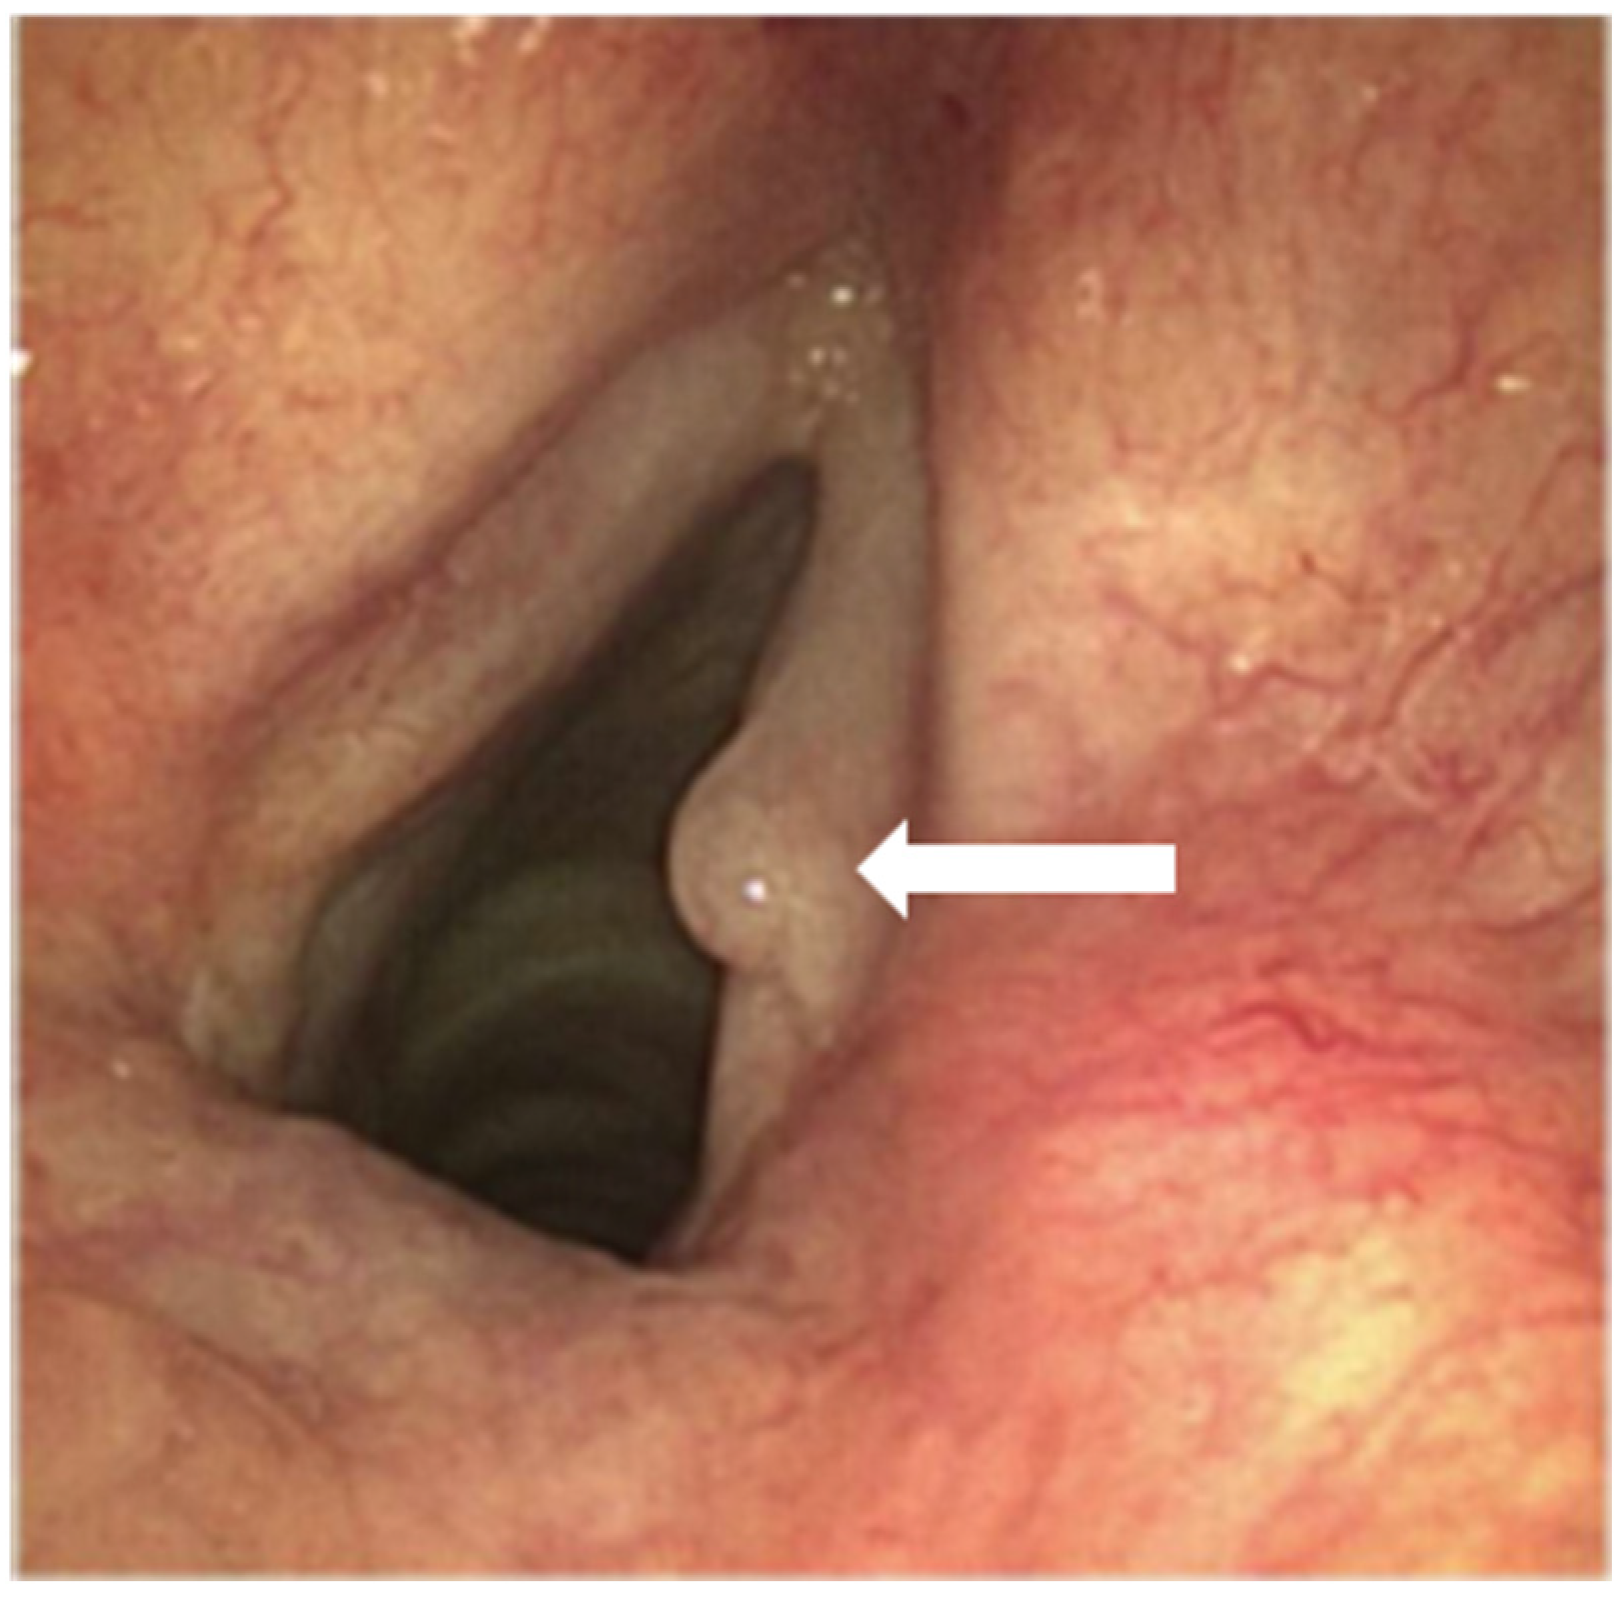

A flexible rhinolaryngoscopy showed an abnormal anatomy of the epiglottis (Figure 1). A laryngeal carcinoma, arising from the anterior side of the epiglottis and extending bilaterally into the aryepiglottic fold, was observed. The entire epiglottis was thickened and rotated to the left, with the vallecula completely filled up. The lateral pharyngeal wall, both arytenoids, and the false and true vocal cords were free of tumor on both sides. The vocal cords showed no abnormalities besides a hyperplastic, polyp-like spot (Figure 2). CT imaging showed that the carcinoma measured 26 × 25 mm axially and 18 mm sagittally. The CT scan obtained the following additional findings: “Filling of the vallecula on the right more than on the left, also involving the lingual side. Primarily right-sided involvement of the aryepiglottic fold at the cranial side. Involvement of the pre-epiglottic fat, with subtle bilateral cranial paralaryngeal fat involvement at the supraglottic level. No involvement of the (cartilaginous) thyroid or hyoid bone. No extension into the base of the tongue. No enlarged lymph nodes”. The histology of the sentinel lymph node in the neck would further determine the treatment algorithm.

Figure 2.

Visualization of the vocal cords with a hyperplastic, polyp-like spot (white arrow) through a flexible rhinolaryngoscope.